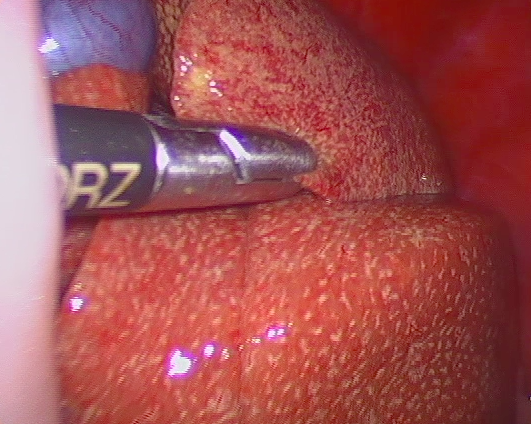

耳鏡検査

耳の中をカメラで確認しながら処置ができます。器具も入れることができるので、異物の摘出や鼓膜周囲の毛を抜いたり、さまざまな検査や処置ができます。耳垢を見ながら除去したり洗浄も可能です。

耳の中のしこりや異物の摘出、慢性の難治性の外耳炎の治療に有効です。